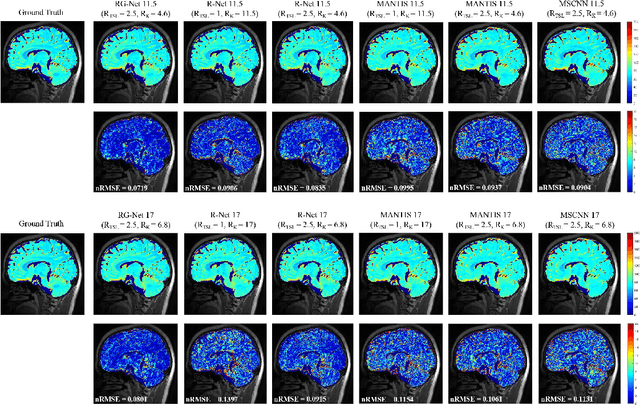

Purpose: To propose a novel deep learning-based method called RG-Net (reconstruction and generation network) for highly accelerated MR parametric mapping by undersampling k-space and reducing the acquired contrast number simultaneously. Methods: The proposed framework consists of a reconstruction module and a generative module. The reconstruction module reconstructs MR images from the acquired few undersampled k-space data with the help of a data prior. The generative module then synthesizes the remaining multi-contrast images from the reconstructed images, where the exponential model is implicitly incorporated into the image generation through the supervision of fully sampled labels. The RG-Net was evaluated on the T1\r{ho} mapping data of knee and brain at different acceleration rates. Regional T1\r{ho} analysis for cartilage and the brain was performed to access the performance of RG-Net. Results: RG-Net yields a high-quality T1\r{ho} map at a high acceleration rate of 17. Compared with the competing methods that only undersample k-space, our framework achieves better performance in T1\r{ho} value analysis. Our method also improves quality of T1\r{ho} maps on patient with glioma. Conclusion: The proposed RG-Net that adopted a new strategy by undersampling k-space and reducing the contrast number simultaneously for fast MR parametric mapping, can achieve a high acceleration rate while maintaining good reconstruction quality. The generative module of our framework can also be used as an insert module in other fast MR parametric mapping methods. Keywords: Deep learning, convolutional neural network, fast MR parametric mapping